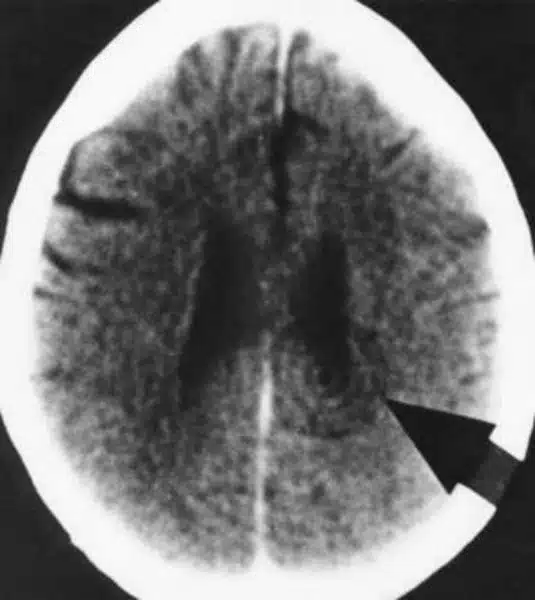

According to the content of the conflict, a particular area of the brain, already determined in advance, has been “switched,” which can be seen from the 1st second on with our

computed tomogram (CT’s), as a so-called Hamer Focus (HH), and therefore a predictable change in the organ, e.g., cell proliferation or cell reduction or a functional disorder, in the so-called cancer equivalents (cancer-like diseases). Switched over here means that the DHS is “only” the switching process to a particular program so that the organism can cope with the unforeseen situation.

On the brain level, we see that during the healing phase, the HH now gets edema, i.e., it turns dark. The rings in the CT become blurred and dark, and the whole relay in the brain swells enormously.

In the brain, both phases naturally have their HH in the same place but in different states: in the conflict-active phase, always with sharply marked circles, the so-called shooting target configuration; in the conflict-resolved phase, the HH is swollen and edematized.